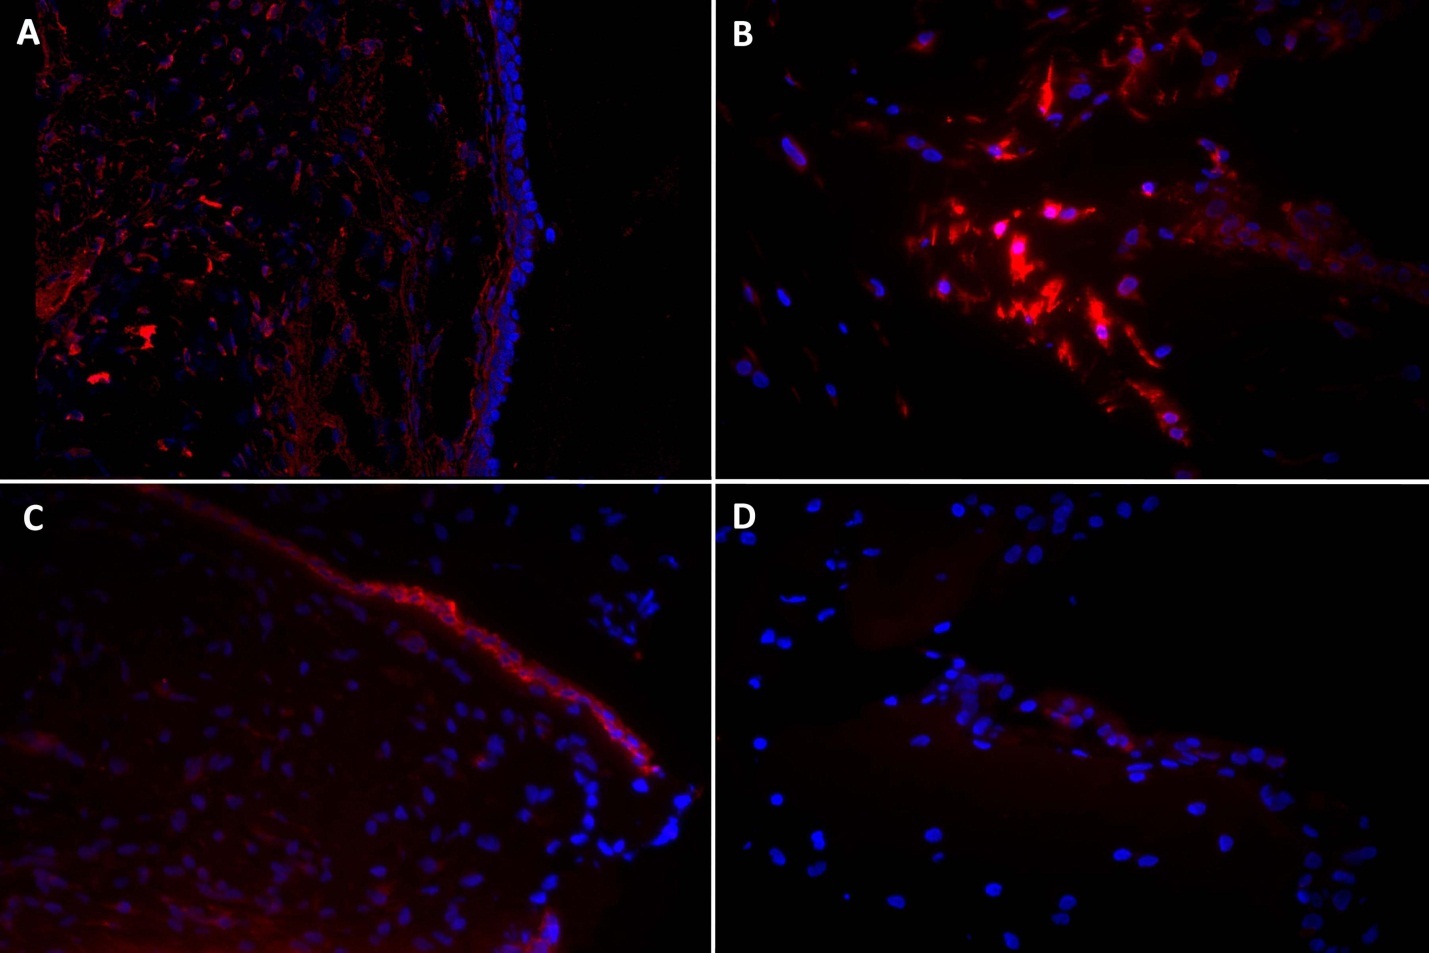

Epithelial differentiation was not induced by EGF and an air interface in this rabbit ASC culture, as indicated by immunohistochemistry. Immunohistochemistry at 14 days was negative for cytokeratin. Vimentin, a general mesenchymal cell marker, was preserved in all cells with and without EGF exposure (Figure 6).

Figure 6.Immunohistochemistry in rabbit true vocal fold (left column), and a fibrin-rASC construct after 14 days in culture with EGF (right column). Vimentin (top row) and cytokeratin (bottom row) appear red, DAPI-labeled nuclei appear blue. A. Vimentin is expressed throughout vocal fold lamina propria. B. Vimentin is expressed in all cells within the construct. C. Cytokeratin is expressed in all cells in the vocal fold epithelium. D. Cytokeratin is indistinguishable from negative control construct samples. Magnification 40x.